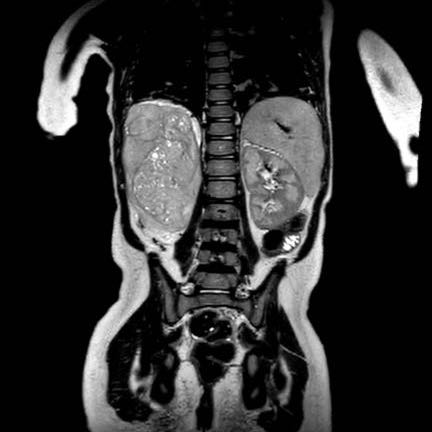

Hình ảnh chuỗi xung T2W mặt phẳng coronal cho thấy một khối u không đồng nhất ở thận trái với các thành phần nang nhỏ.

Khối u ngấm thuốc kém hơn so với phần nhu mô thận bình thường còn lại ở ngoại vi.

Các thành phần đặc của khối u cho thấy hạn chế khuếch tán rõ rệt (mũi tên).

Đây là u Wilms ở bé trai năm tuổi. Hóa trị tiền phẫu được thực hiện theo phác đồ Umbrella của SIOP-RTSG, sau đó tiến hành cắt thận.